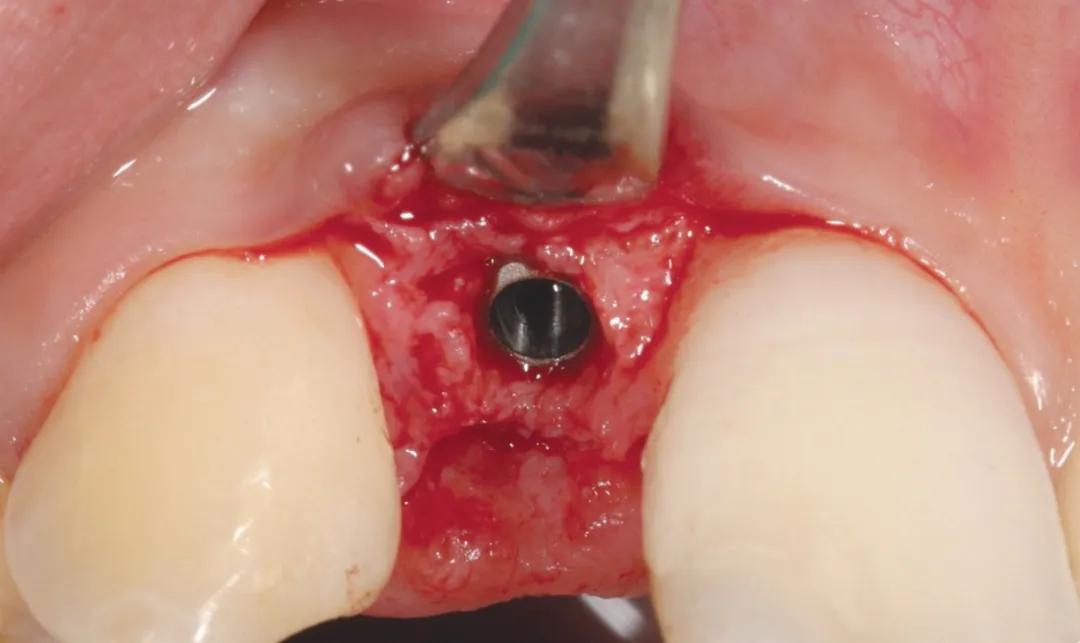

2 号病例 - Patrick EXBRAYAT 医生(图 21 至 35)

22 岁患者,23 异位,行正颌外科种植术后 22 出现严重根吸收。

图 24 :植入 Axiom® 2.8 x 14 种植体。

图 25 :种植体就位。